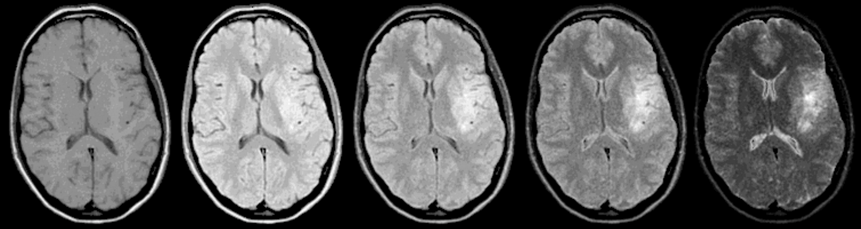

Figura 10-05:

The necessity of image acquisitions with different pulse sequence parameters: Brain, transverse view. SE sequence: TR = 1500 ms; TE from 15 ms to 225 ms. B₀ = 0.5 T.

On the more T2-weighted images, there is a clear­ly visible lesion: an old brain infarction. If you would just perform a T1-weighted study, only very suspicious radiologists will describe possible pa­tho­lo­gi­cal changes: there is a slight mass effect.

Simulation software: MR Image Expert®